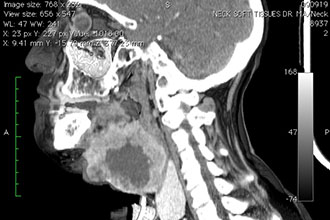

| Компьютерная томография (КТ) гортани | Детальная визуализация гортани и окружающих тканей; высокая точность диагностики | Ионизирующее излучение; высокая стоимость; не всегда доступна |

| Магнитно-резонансная томография (МРТ) гортани | Отличная визуализация мягких тканей; без ионизирующего излучения | Высокая стоимость; длительность процедуры; может быть противопоказана пациентам с металлическими имплантатами |